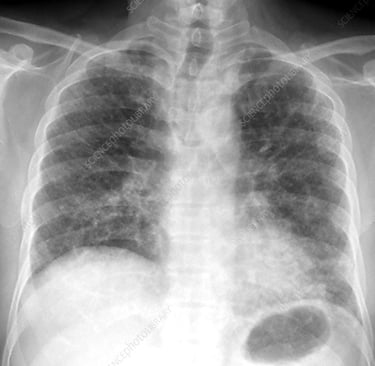

3. İdiyopatik Pulmoner Fibrozis (IPF): "Bilinmeyen"den "Belirlenmiş"e

Dünyada yaklaşık 3 milyon kişinin mücadele ettiği İdiopatik Pulmoner Fibrozis, sıklıkla 50 yaşın üzerinde ve genellikle erkeklerde görülüyor. Tıpta "idiyopatik" terimi, nedenini henüz bulamadığımız durumlar için kullanılan bir itiraftır. Ancak de Dombal tarzı Bayesyen analiz ve fonksiyonel tıp merceğiyle baktığımızda, IPF (idiopatik Pulmoner Fibrozis) bir tesadüf değil, bir "multi-hit" (çoklu darbe) sonucudur.

4. Teşhisin Bayesyen Gücü: Algoritmik Yaklaşım

Tanı koyarken sezgilere değil, olasılıklara dayanmalıyız. Yüksek çözünürlüklü BT (HRCT) ve klinik bulguların tanısal gücü:

HRCT (UIP Pateni) Sens: %90 - 95 Spe: %90 - 98 LR+ 9.5 - 45 LR- 0.05

Not: LR+ değerinin 10'un üzerinde olması, o bulgunun tanıyı neredeyse kesinleştirdiğini gösterir. HRCT’deki tipik UIP (Olağan İnterstisyel Pnömoni) görünümü, Bayesyen analizde "post-test olasılığını" %95’in üzerine çıkarır.